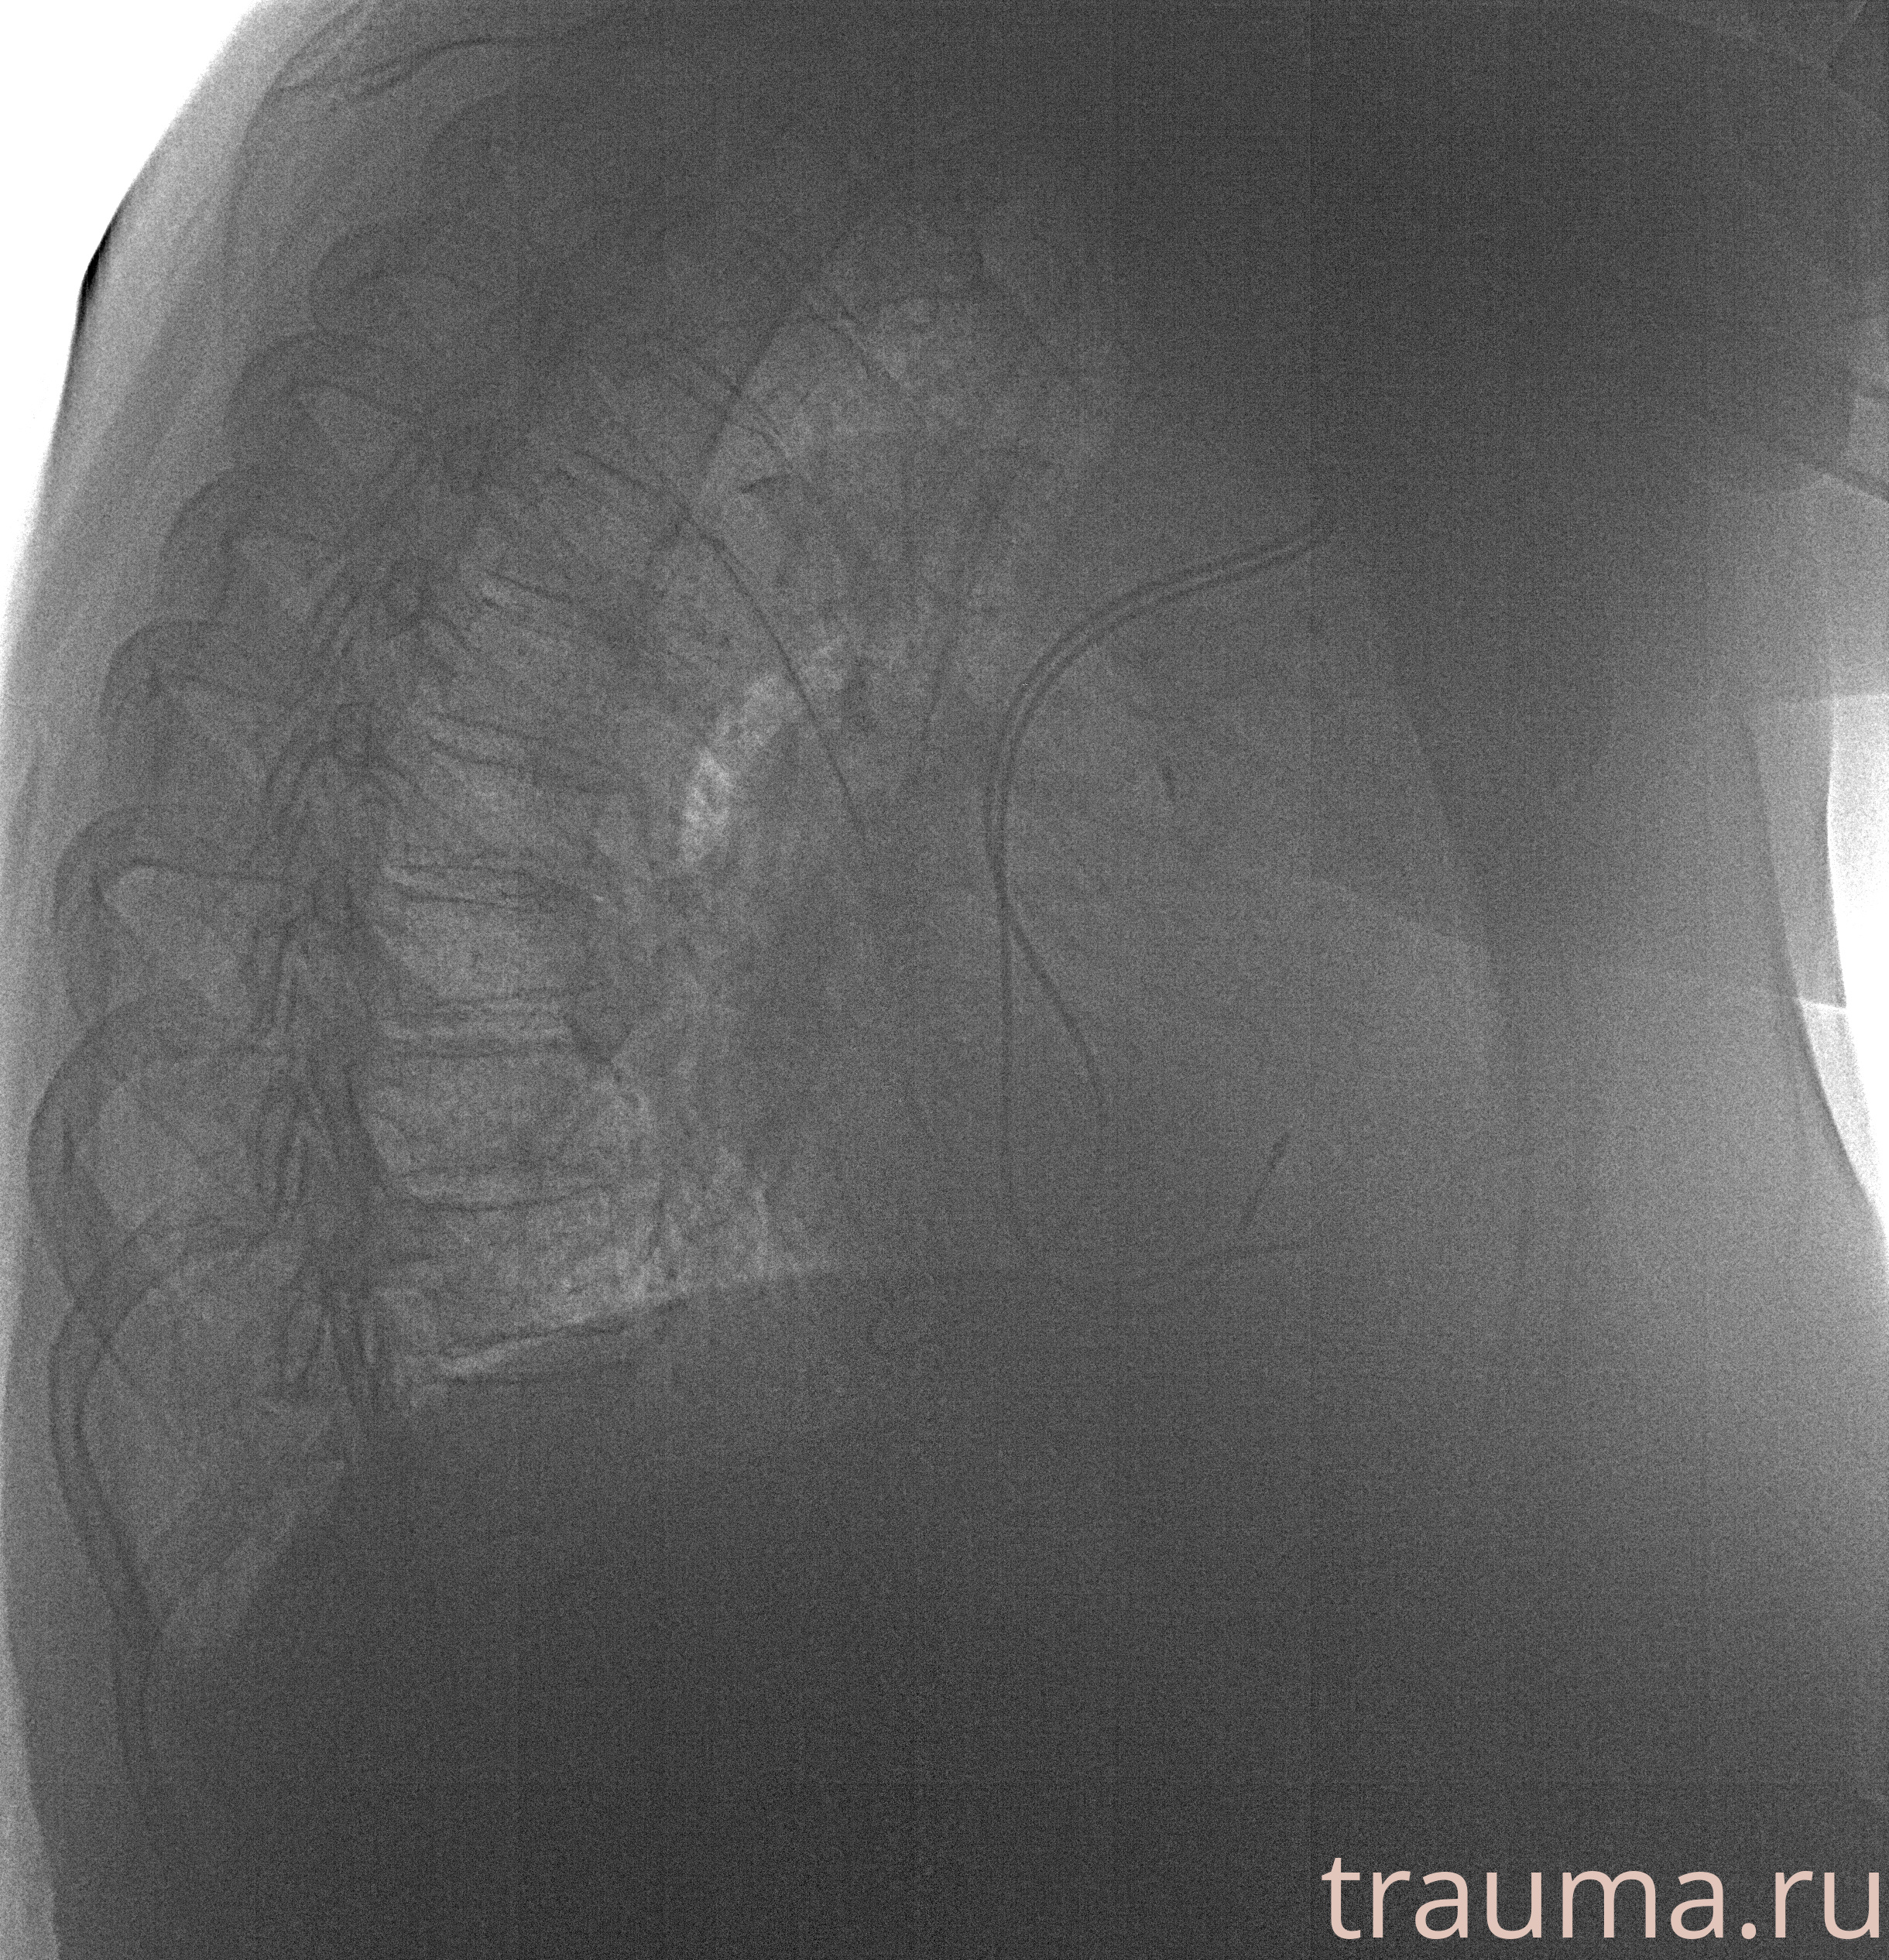

Рентгенограммы

Рентген на дому: по вашему адресу приезжает врач-рентгенолог, травматолог-ортопед с мобильным рентгеновским аппаратом, проводит диагностику травмы или заболевания, делает необходимые рентгенограммы, дает рекомендации по дальнейшему лечению. Получить качественные снимки в домашних условиях возможно благодаря уникальной методике, разработанной МосРентген Центром для института  Склифосовского